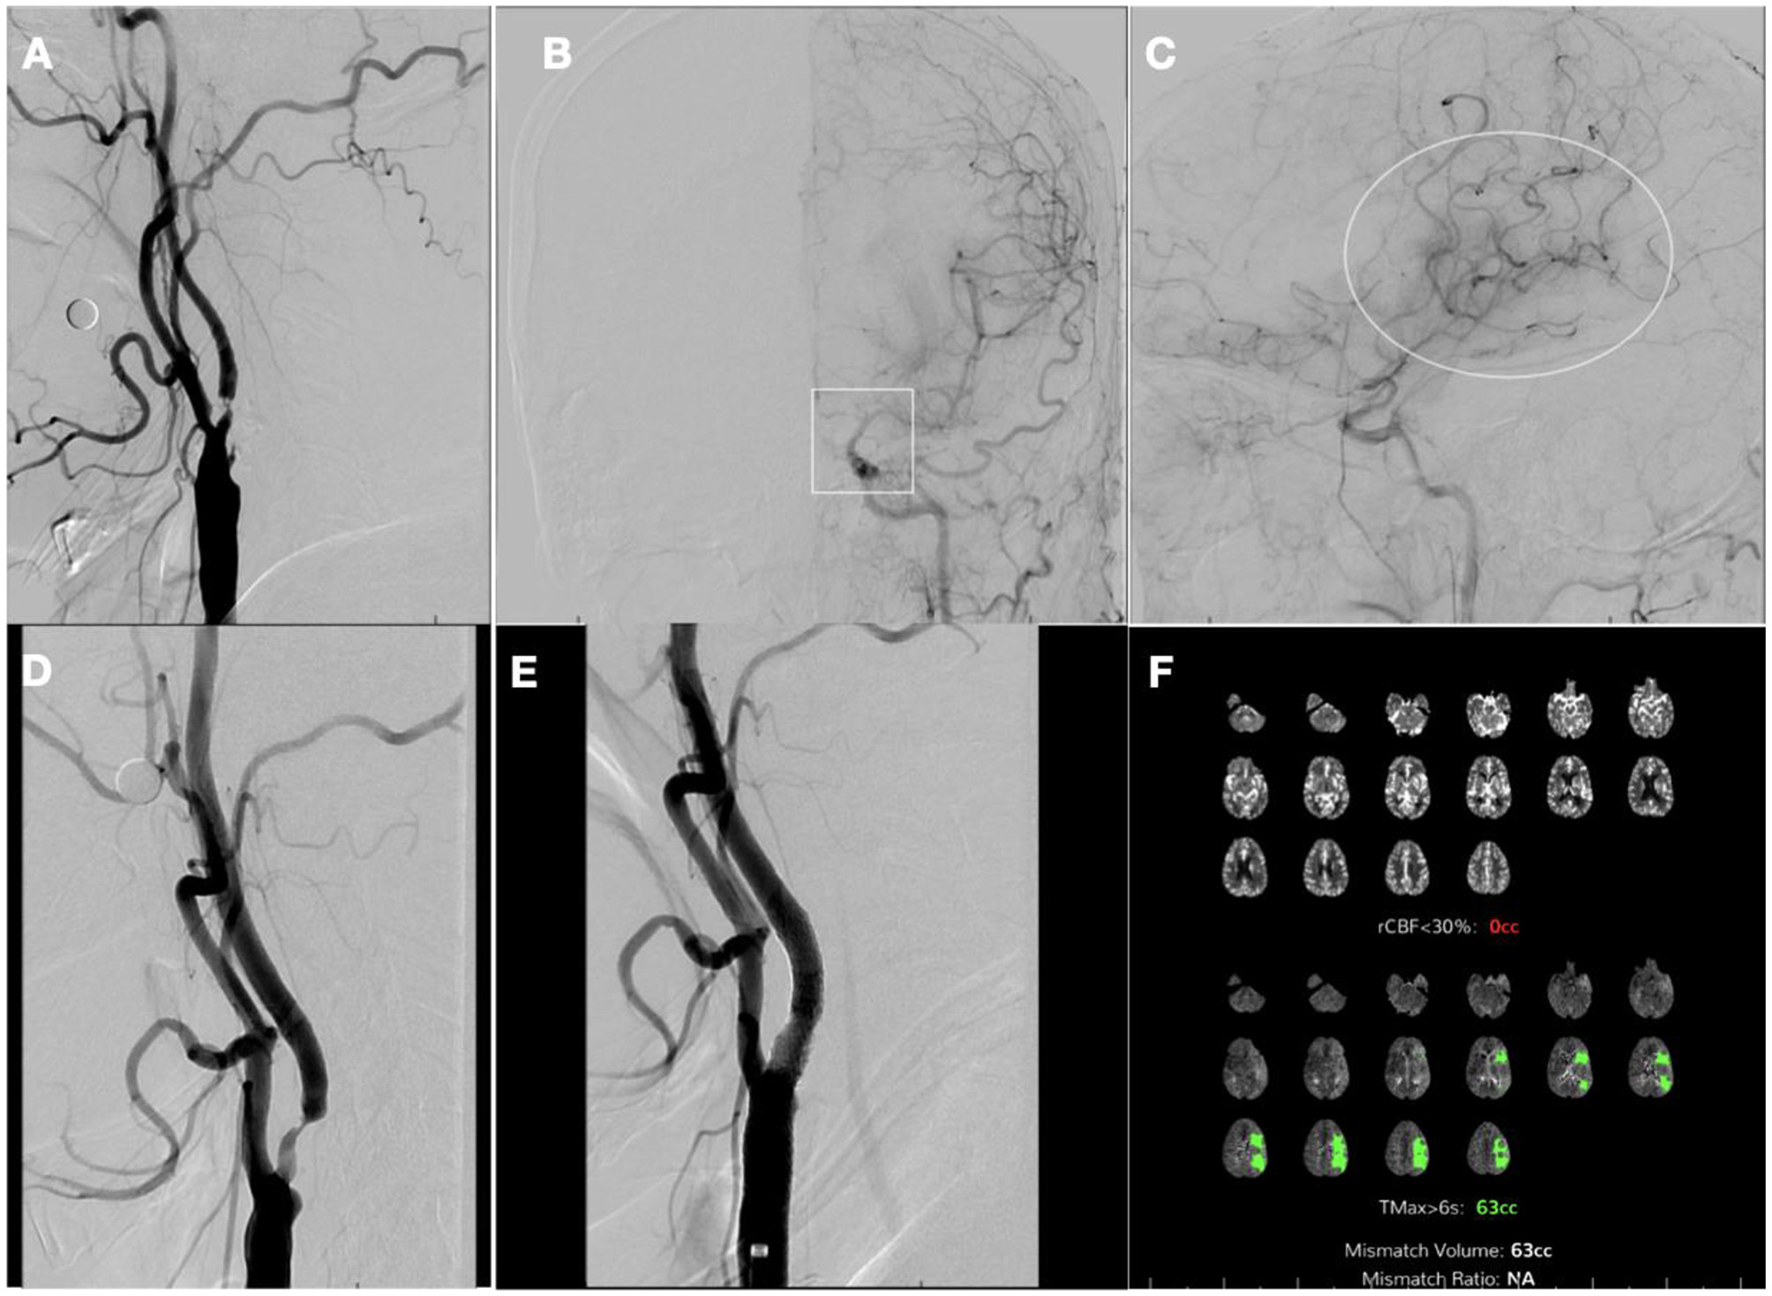

A 62-year-old male with a history of hypertension, atrial fibrillation post-ablation not on anticoagulation, and HIV on highly active antiretroviral therapy woke up with dysarthria and right-sided upper extremity and facial weakness. He was immediately taken to our hospital, ~7.5 h after last seen normal and 4 h from the midpoint of sleep. The National Institute of Health Stroke Scale (NIHSS) score at presentation was 6. Non-contrast head computerized tomography showed a dense left middle cerebral artery (MCA) sign (Figure 1A) and decreased gray-white matter differentiation on the left lentiform nucleus, with an Alberta Stroke Program Early CT Score of 9 (Figure 1B). Computed tomography (CT) angiogram showed severe right ICA stenosis and complete occlusion of the left proximal ICA (Figure 1C). There was a tandem occlusion of the M1 segment of the left MCA, but the left proximal ACA was perfused via a patent Acomm (Figure 1D).

Figure 1. Pre-thrombolytic non-contrast computerized tomography (CT), CT angiogram (CTA), and CT perfusion (CTP). (A) Axial CT head showing left dense middle cerebral artery (MCA) sign; (B) Axial CT Head, showing decreased gray-white matter differentiation on left lentiform nucleus; (C) CTA of neck coronal view: proximal left internal cerebral artery occlusion; (D) flow reconstitution of distal ICA flow and occlusion of proximal left MCA. (E) CTP showing core of 8cc, penumbra of 86cc, and mismatch ratio 10.8 on the left MCA territory.

CT perfusion (CTP) was pursued to guide acute management, and it showed a core infarct volume of 8cc in the left MCA territory and a penumbra volume of 86cc, with a mismatch volume of 78cc and a ratio of 10.8 (Figure 1E). Upon those findings, the patient received IVT and was taken to the neurointerventional suite for possible mechanical thrombectomy (MT) of the left ICA.